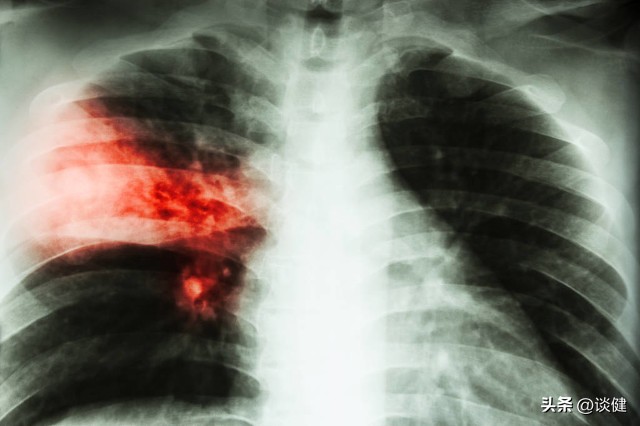

临床上也有数起因*子烟电**造成肺伤害的案例,其中不乏青少年族群。曾一位15岁少年出现呼吸喘、咳嗽、上腹痛、呕吐等症状,经胸部X线及胸部CT检查发现双侧肺炎,排除感染及其他原因后,经过询问,少年坦承11岁起开始抽*子烟电**,烟龄4年,确认是由*子烟电**造成的肺部损伤。